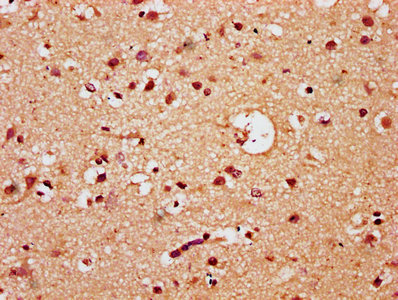

IHC image of CSB-PA887024LA01HU diluted at 1:300 and staining in paraffin-embedded human brain tissue performed on a Leica BondTM system. After dewaxing and hydration, antigen retrieval was mediated by high pressure in a citrate buffer (pH 6.0). Section was blocked with 10% normal goat serum 30min at RT. Then primary antibody (1% BSA) was incubated at 4°C overnight. The primary is detected by a biotinylated secondary antibody and visualized using an HRP conjugated SP system.

IHC image of CSB-PA887024LA01HU diluted at 1:300 and staining in paraffin-embedded human glioma performed on a Leica BondTM system. After dewaxing and hydration, antigen retrieval was mediated by high pressure in a citrate buffer (pH 6.0). Section was blocked with 10% normal goat serum 30min at RT. Then primary antibody (1% BSA) was incubated at 4°C overnight. The primary is detected by a biotinylated secondary antibody and visualized using an HRP conjugated SP system.